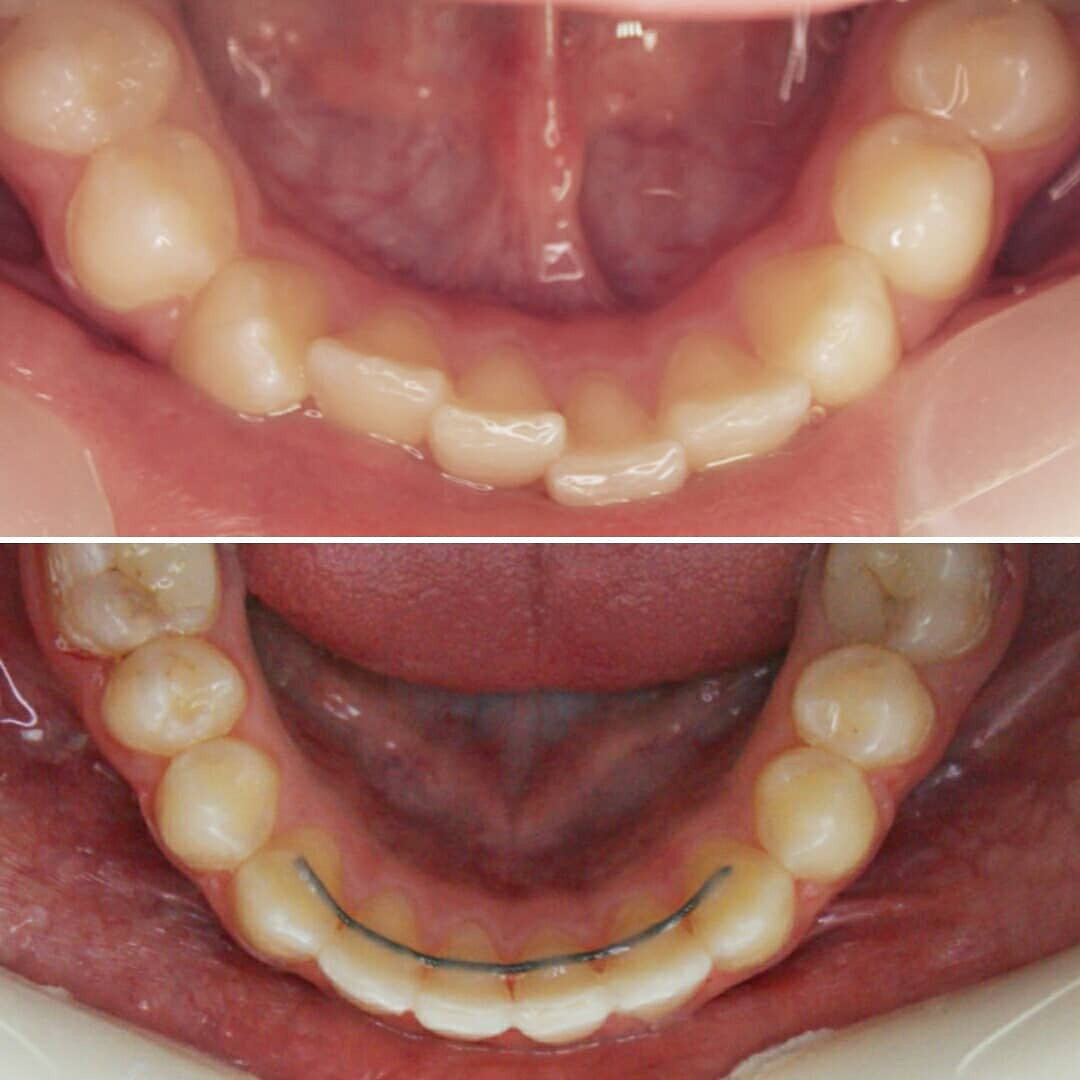

Эта фраза знакома многим ответственным родителям, которые привели на приём к ОРТОДОНТУ своего ребёнка в 5-10 лет, заподозрив проблему или понимая, что места постоянным зубам откровенно не хватает! Горькая правда в том, что брекеты - не волшебное средство от всех проблем, они "расставляют" зубы внутри сформированого объёма челюсти, но никак не влияют на её рост. Родители ждут, а тем временем драгоценное время, когда ребёнок растёт, уходит... Во взрослом возрасте приходится удалять здоровые зубы или прибегать к ортогнатической хирургической операции. 📸 На фото узкая нижняя челюсть, места постоянным зубам нет, боковые резцы прорезываются "вторым рядом".

✅ Помогаем с помощью расширяющей дуги, пружины и зацепных элементов, которые зафиксированы на МОЛОЧНЫЕ зубы

❓Почему на нижней челюсти зубы тоже прорезываются неровно?

▶️ При сужении верхней челюсти сужается и нижняя, так как нижняя под верхнюю "подстраивается". Верхняя челюсть словно зажимает в тиски нижнюю челюсть и тормозит её рост.

❓Нижнюю челюсть тоже нужно расширять?

▶️ При достаточном расширении верхней челюсти, нижняя начинает "расти" и "подстраиваться" под верхнюю сама. Такая адаптация может занять год. Но часто мы помогаем расширению нижней челюсти (дополнительные аппараты, гимнастика для мышц лица и рта, др.)